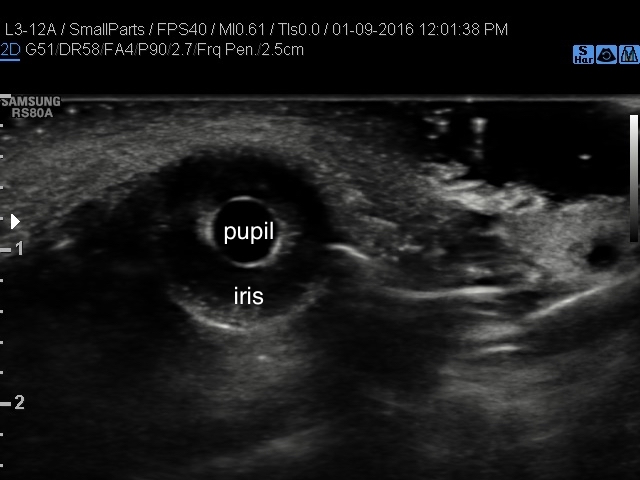

以下為正常的瞳孔和虹彩的超音波影像,

影片中瞳孔也對應光線有不一樣的大小變化,

用另一種視角來看瞳孔也是很新奇的體驗 !!